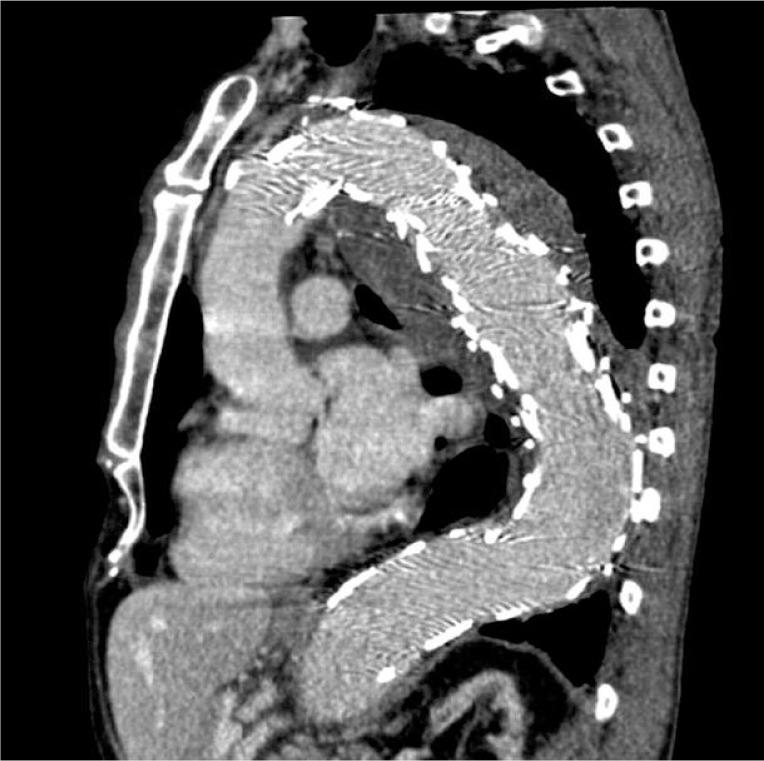

Hemoptysis as a first symptom of endoleak after thoracic endovascular aortic repair, which caused aortic rupture and required complex management.

Thoracic endovascular aortic repair (TEVAR) has become the most common procedure in the treatment of thoracic aorta aneurysms. However, potential long-term complications of this technique could be life-threatening. Hemoptysis is a common symptom of lung tumor, especially cancer. On the other hand, hemoptysis can also be caused by bronchitis, tuberculosis, mycosis, and trauma. In this case report, we present a patient with hemoptysis and lung tumor suggesting lung cancer, which was a unique symptom of type IA endoleak after TEVAR and led to rupture of the thoracic aneurysm. It was decided to perform next an endovascular procedure due to the severe state of the patient. Next the thoracotomy was performed because drainage of the left pleural cavity was unsuccessful. In the last stage bronchoscopy was needed to remove the thrombus, which occluded the left main bronchi. Successful management has led to the patient's full recovery. Despite justified popularity of endovascular procedures in the treatment of thoracic aorta aneurysms, we should remember about potential long-term complications. Hemoptysis could be a unique symptom of the endoleak after TEVAR and treatment of such complications could be complex and demanding.